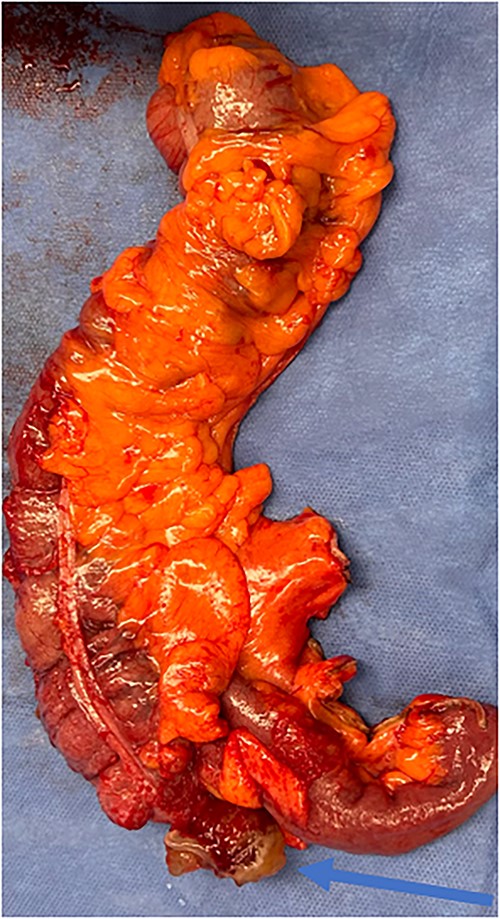

An exploratory laparotomy with a midline incision was performed. Upon inspection of the abdominal cavity, there was no evidence of metastatic disease to the peritoneum, omentum, or liver. A perforated mucinous mass with mucinous collection was identified in the right lower quadrant by the appendix with an additional mucinous collection in the pelvis. Given the appendiceal and cecal involvement, the decision was made to perform a right hemicolectomy and primary anastomosis. Given that this was favored to be a malignant process intraoperatively, the decision was made to perform a right hemicolectomy over a limited ileocolic resection. Lymph nodes were also included due to the extent of the surgical resection. The specimens were sent to pathology. The abdomen was further inspected and subsequently closed (Figs 3–5). The patient tolerated the procedure well, was extubated in the operating room, and recovered in the post-anesthesia care unit in stable condition. The patient was observed postoperatively and was discharged home on postoperative Day 8. The duration of follow-up is 4 months without clinical concerns during follow-up. The final pathology of the specimens revealed LAMN with perforation and associated calcifications. The proximal and distal resection margins were free of neoplasia, and 42 lymph nodes were negative for tumor. There was presence of acellular mucin in the tissue sample, suggesting a favorable prognosis according to previous studies demonstrating that 96% of patients with acellular extra-appendiceal mucin were disease-free at 52 months [5]. Follow-up via surveillance magnetic resonance imaging (MRI) every 6 months, and colonoscopy were recommended. The patient was referred for blood testing, including the tumor marker carcinoembryonic antigen (CEA), which has been unremarkable.

Perforated mucinous mass at the base of the appendix (blue arrow).

Perforated mucinous mass at the base of the appendix (blue arrow) and mucin collection at the region of the appendix (yellow arrow).

Specimen including terminal ileum, ascending colon containing the perforated mucinous mass at the base of the cecum (blue arrow).